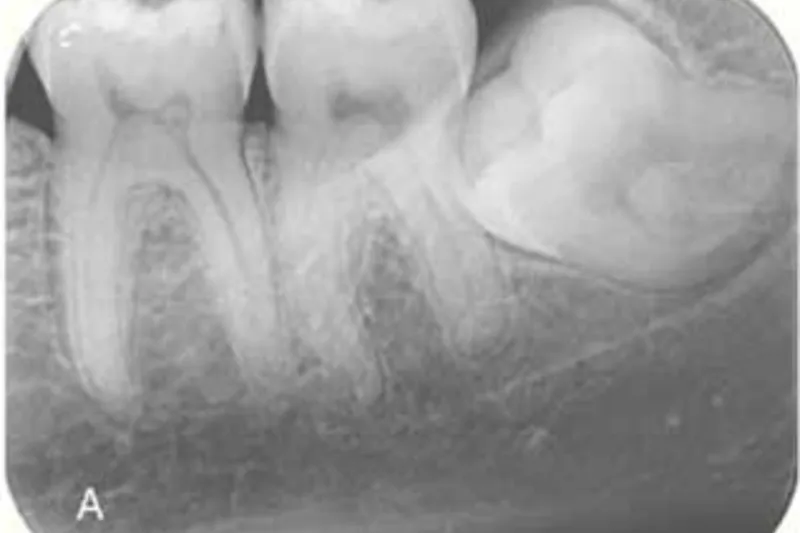

Det er lege artis at foretage en røntgenundersøgelse forud for kirurgisk fjernelse af mandiblens tredjemolar (M3), og intraoral periapikal eller panoramaoptagelse anses for førstevalg, mens Cone Beam Computed Tomografi (CBCT) kan anvendes i særlige patienttilfælde, hvor der foreligger et ønske om en mere detaljeret radiologisk undersøgelse af relation mellem canalis mandibulae og rodkomplekset af M3 samt eventuelt omkringliggende sygdom. Imidlertid er det vist, at radiologiske fund på CBCT hverken ændrer på behandlingen af M3 eller på patientens postoperative forløb, herunder forekomsten af neurosensoriske forstyrrelser sv.t. n. alveolaris inferior (NAI). Derudover er det vanskeligt at identificere, hvilke radiologiske tegn der kan benyttes som prædiktorer for en neurosensorisk forstyrrelse sv.t. NAI. De klassiske syv panoramategn er således ikke længere valide. Nyere forskningsresultater på et højere evidensniveau har vist, at tilfælde, hvor M3’s rødder strækker sig kaudalt for den nedre begrænsning af c. mandibulae, er forbundet med en øget forekomst af permanent neurosensorisk forstyrrelse. Den generelle anbefaling vedrørende radiologisk undersøgelse før kirurgisk fjernelse af M3 er derfor, at 2D radiologisk undersøgelse er tilstrækkeligt i hovedparten af de patienttilfælde, hvor M3 skal fjernes.

A radiographic examination is required before removal of mandibular third molars (M3). An intraoral or panoramic examination should always be the first choice, and cone beam computed tomography (CBCT) can be considered in special patient cases, where the relation between the mandibular canal and M3 needs to be assessed in a more detailed radiographic examination and in case of suspected pathology related to M3. For mandibular third molars, it has been shown that CBCT changes neither the treatment plan nor the postoperative outcome for the patient including the incidence of neurosensory disturbances of the inferior alveolar nerve. Moreover, it is difficult to identify radiographic risk factors for a neurosensory disturbance of the inferior alveolar nerve. The seven classic signs in panoramic images are no longer considered valid. Recent research on a higher level of evidence has found that if the root of third molar extends below the lower border of the mandibular canal, there is an increased risk of permanent neurosensory disturbances. Overall, a 2D image is sufficient in the majority of cases before surgical intervention.